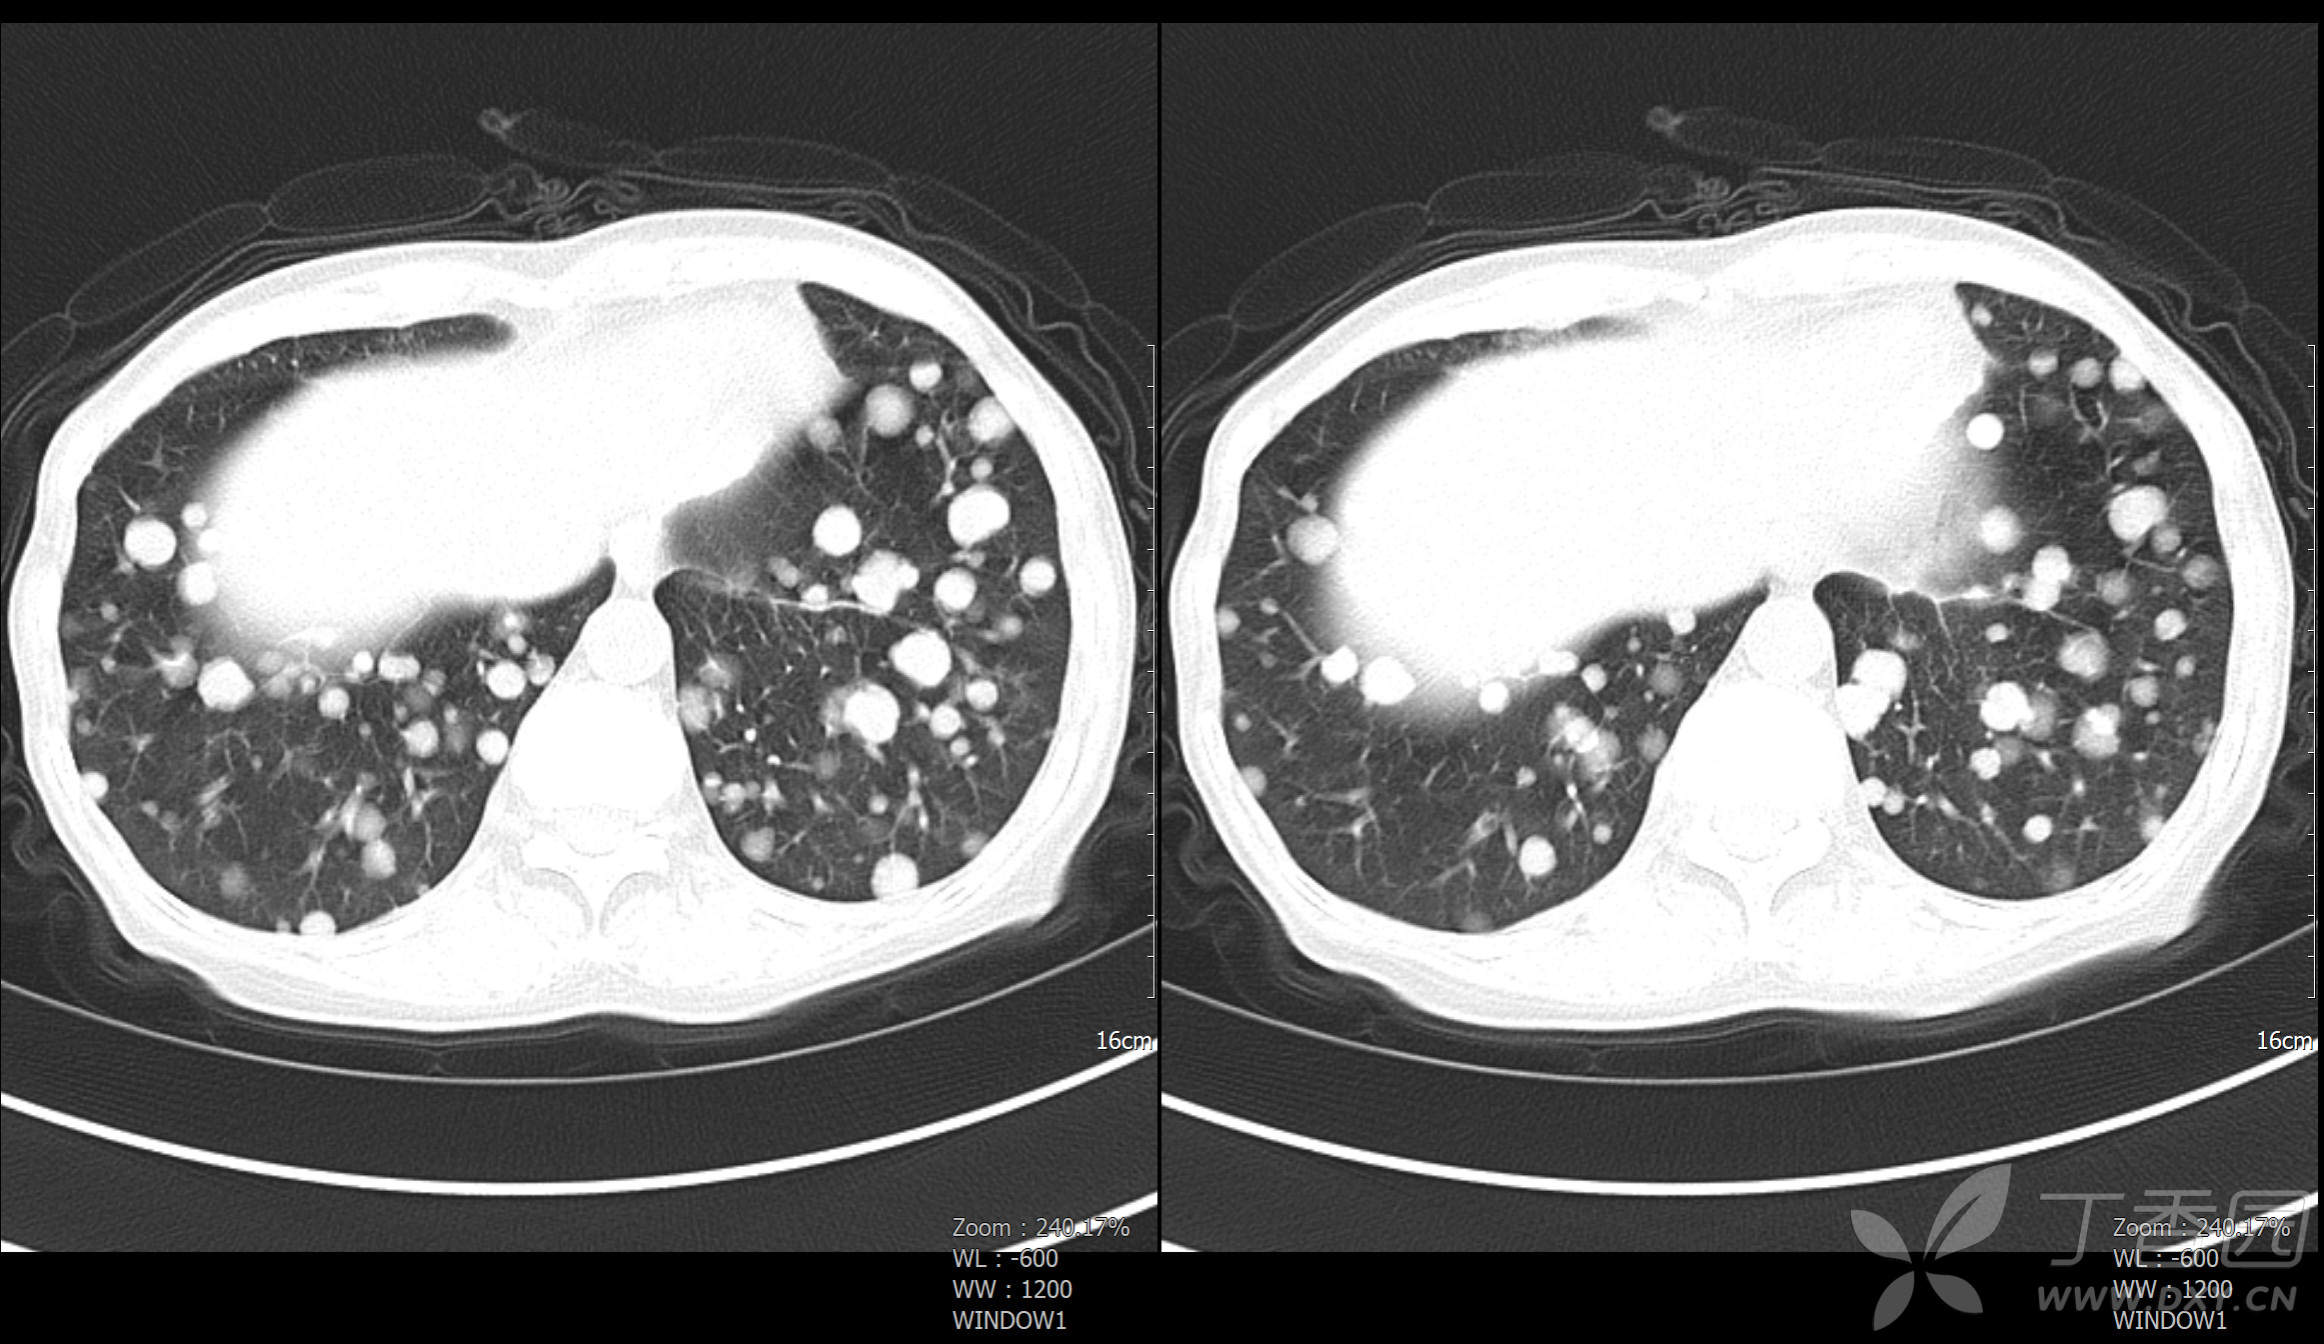

典型病例066:肺癌肺转移,密集恐惧症者忌 - 丁香园论坛

图片尺寸2324x1344